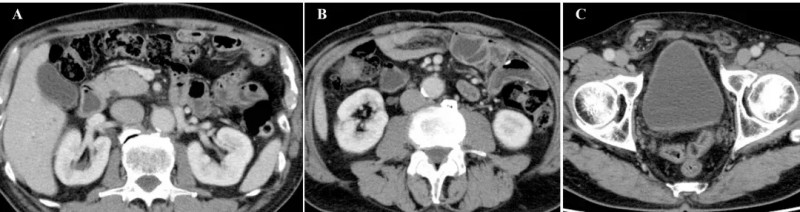

完成8次治疗后1个月,患者症状与影像学表现均大幅改善:恶性腹水完全消退,腹胀、腿部水肿消失,食欲恢复,原发病灶及转移性淋巴结持续缩小,腹膜播散的影像学特征已不明显,腹腔内大网膜(脂肪性粘稠组织)消失(详见下图A),仅右侧腹股沟疝因既往大量腹水导致的腹压影响仍持续存在(详见下图C)。此外,治疗无严重不良反应,患者恢复正常活动,截至首次给药后54个月仍无复发。

▲图源“Cureus”,版权归原作者所有,如无意中侵犯了知识产权,请联系我们删除